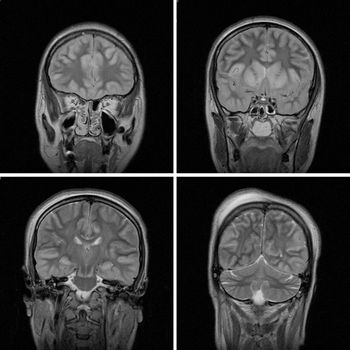

This case is a 26-year-old female in whom MRI imaging was done24 hours after an attempted hanging episode.